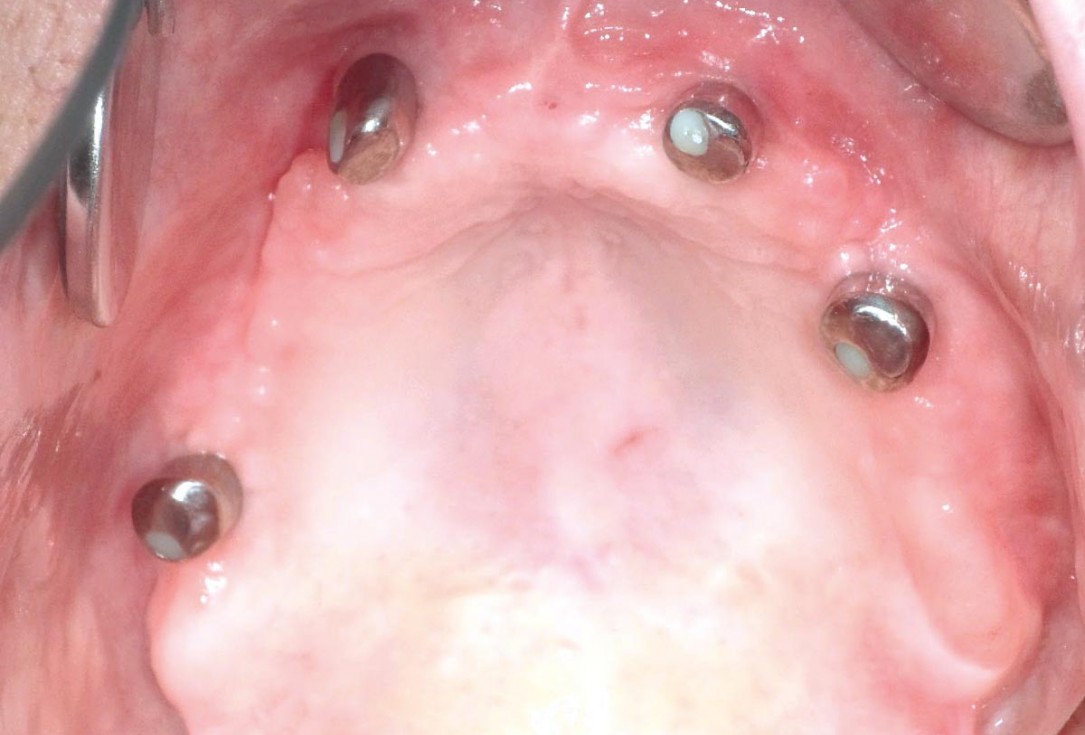

15/23 - Implant insertion after six months: four Straumann® Bone Level SLA® 4.1 mm implants

Full arch reconstruction of the maxilla with maxgraft® bonebuilder - Dr. M. Erbshäuser